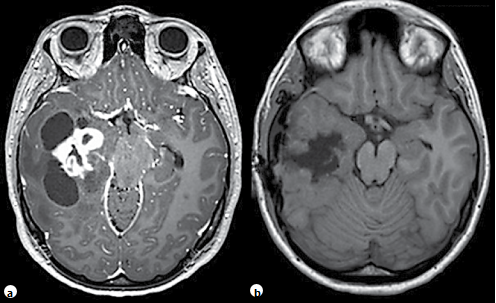

圖1:一名11歲兒童的右顳部腫瘤伴有多發(fā)囊腫并增強(qiáng)了固形部分的情況下,術(shù)前(a)和術(shù)后(b)進(jìn)行的軸向?qū)Ρ萒1加權(quán)MRI。